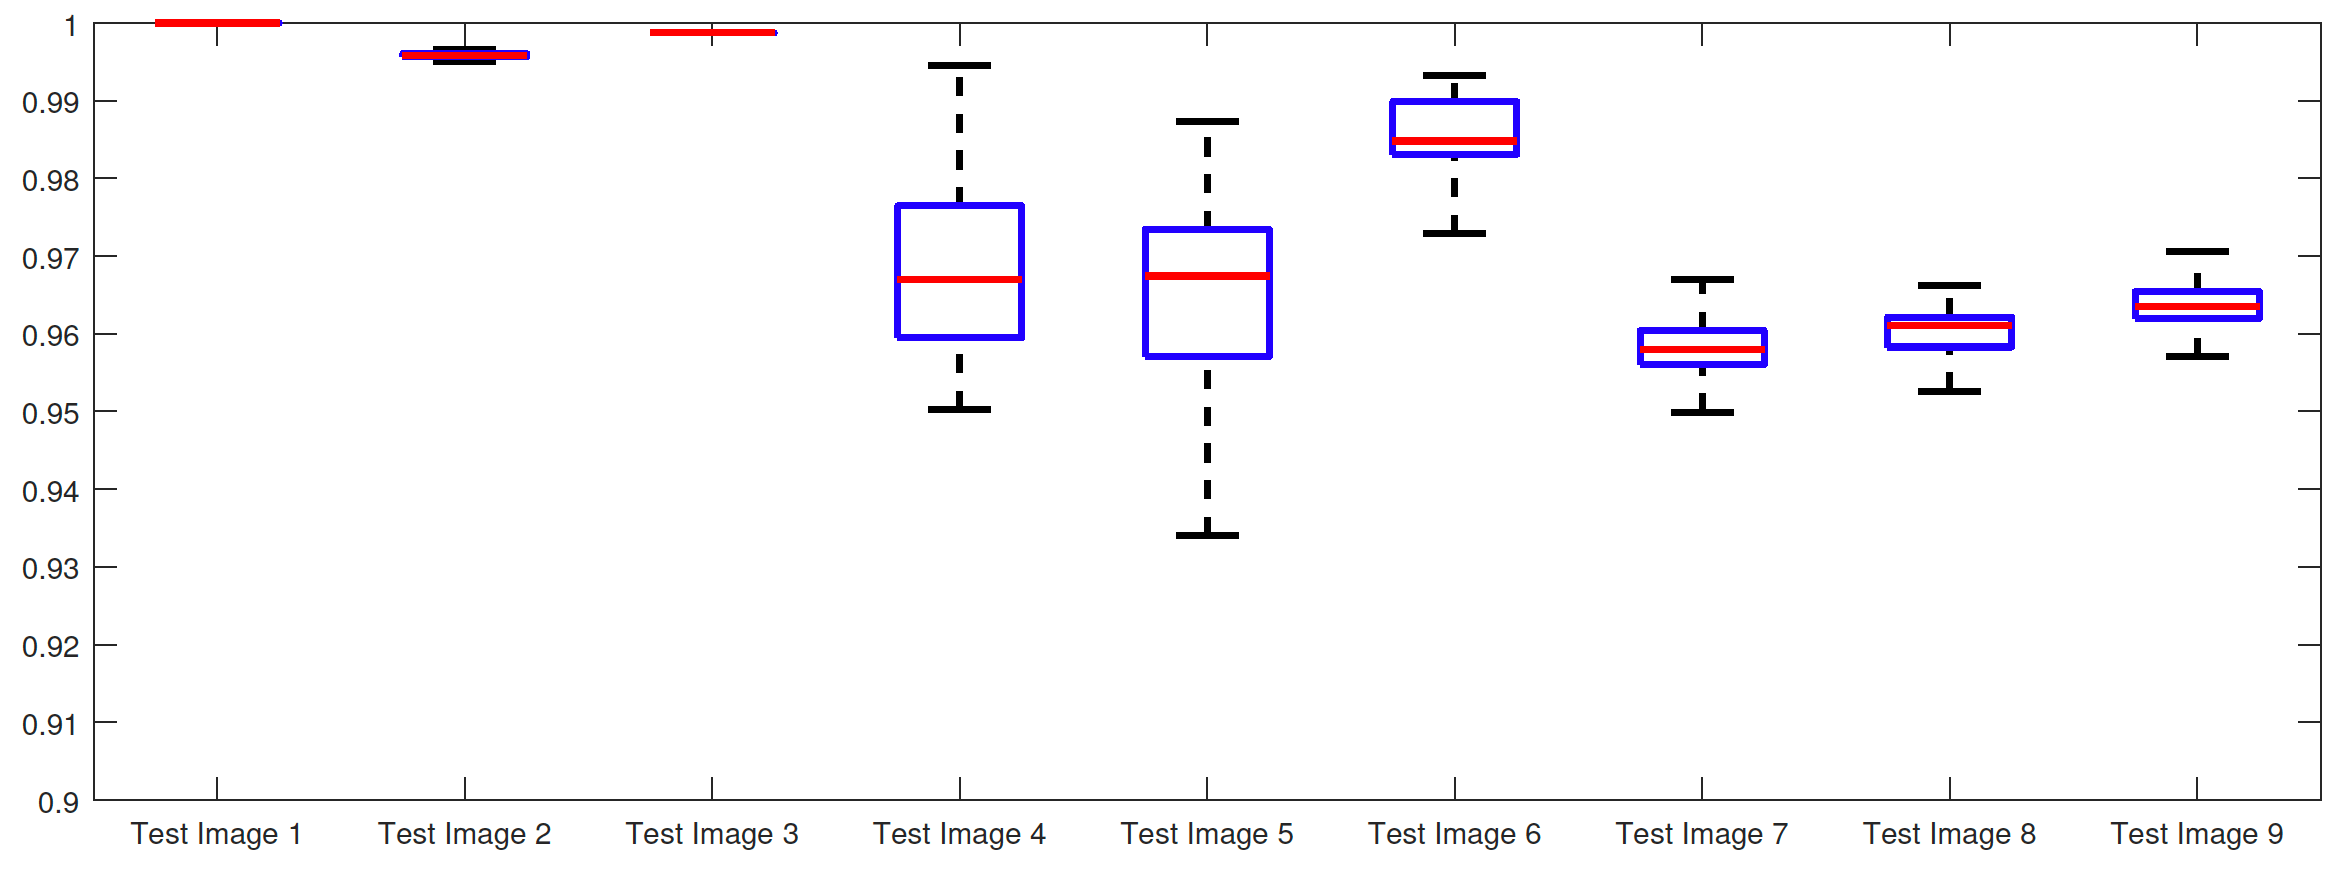

We regard neither of these assumptions to be too onerous on a user, and are quite consistent with practical use. To perform this test, we randomly choose sets of 3 marker points and run each algorithm using them. The parameters and are fixed at those which gave the optimal TC values in Table 1. For each set of marker points we compute the corresponding TC value of applying the proposed model with this input. The results for each image are summarised by boxplots in Fig. 15 with examples of the worst results, excluding outliers, shown in Fig. 16. Here, it can be seen that the worst result often outperforms the optimal results of the alternative models considered, which is impressive. Below we discuss the results for the test images, by again splitting them into synthetic and real images. Based on the authors’ implementation of CAC and SRW it was not possible to generalise the input in this way. Instead we make direct comparisons of input in the next section.

Synthetic Images. For the Test Images 1–3 we achieve near perfect segmentations in all cases, shown by the mean TC being between 0.99 and 1.00 in all cases (for Test Image 1, the mean is precisely 1.00) and a small variance around the mean. Therefore, we can conclude that for images of this type, where the foreground is homogeneous, our method is very robust to user input. Essentially, any reasonable set of markers should produce excellent results. It should be noted that the optimal results from comparable approaches are less than the mean result of random tests for our method (except for SRW). This can be observed in Table 1. Furthermore, these methods often fail completely. This is a key result highlighting the advantages of our method. In visually simple cases (Test Images 1–3) our new data fitting term is an improvement on existing approaches by modifying the underlying assumptions involved.

[\capbeside\thisfloatsetupcapbesideposition=left,top,capbesidewidth=1.5in]figure[\FBwidth]

Real Images. In all cases for Test Images 4–9 the mean values show that the segmentation results are highly accurate. Also, we notice that the variances are very reasonable demonstrating the robustness of varying the user input. This is an important aspect of selective segmentation, and highlights the advantages of the proposed fitting term. For Test Images 4–6 we observe more variability in the accuracy due to minor intensity inhomogeneity in the foreground. This means randomising the user input will be more sensitive. However, we can see that the results are very good with the mean accuracy being competitive with the optimal accuracy of comparable methods. In the case of the lung CT images (Test Images 7–9) the variance in TC values is very small, due to the homogeneity of the foreground. Again, it is important to compare the results of random results using our proposed model to the optimal result of comparable methods. For these images all of the methods (except GAV,CAC, and SRW) have at least one TC value below 0.9. However, GAV requires the tuning of additional parameters whilst the proposed model does not. The results for CAC and SRW also rely on extensive requirements of the user input to achieve this accuracy, whereas random input compares favourably here. Compared to GAV, we can see that the mean of our tests is similar to the optimal value of GAV. One exception is for Test Image 9 (shown in Fig. 14), where there is a significant gap in favour of our model. Again, from Fig. 16, we can see that the worst result of randomising the user input for the proposed model is competitive with the optimal results of the alternatives. This is one of the most encouraging aspects of the tests; the proposed model is remarkably robust to varying user input. This proves that successful results with minimal, intuitive user input is possible for a range of examples.